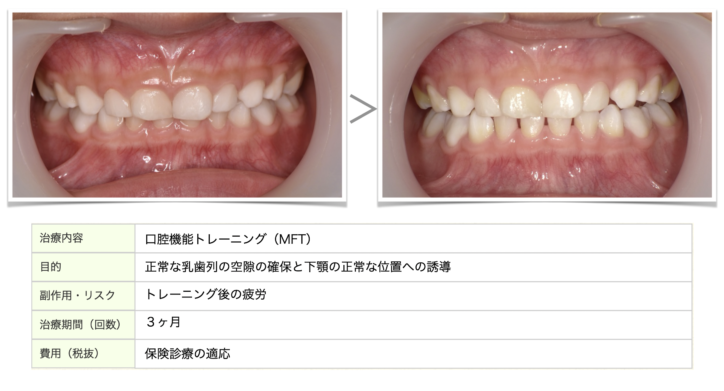

上記症例は、虫歯や歯肉炎予防で通院中のお子様に、バクシネーターメカニズムに基づいた食育とトレーニングをした結果の変化です。乳歯の歯の隙間ができて、永久歯がは萌えるスペースができ、下顎も下がっているところから前方に誘導されいることが分かります。

6歳までにお顔の骨の成長の80%が成長します。

虫歯や歯肉炎だけでなく、歯並びに関しても

①早期に問題を見つけ

②早期に『なぜ?』を親御さんと共に考えて

③早期に私たちと一緒に問題を解決する

ことで、歯並びの予防につながります。

お子様のお口に関することで少しでも気になることがございましたらお気軽にご相談下さい。